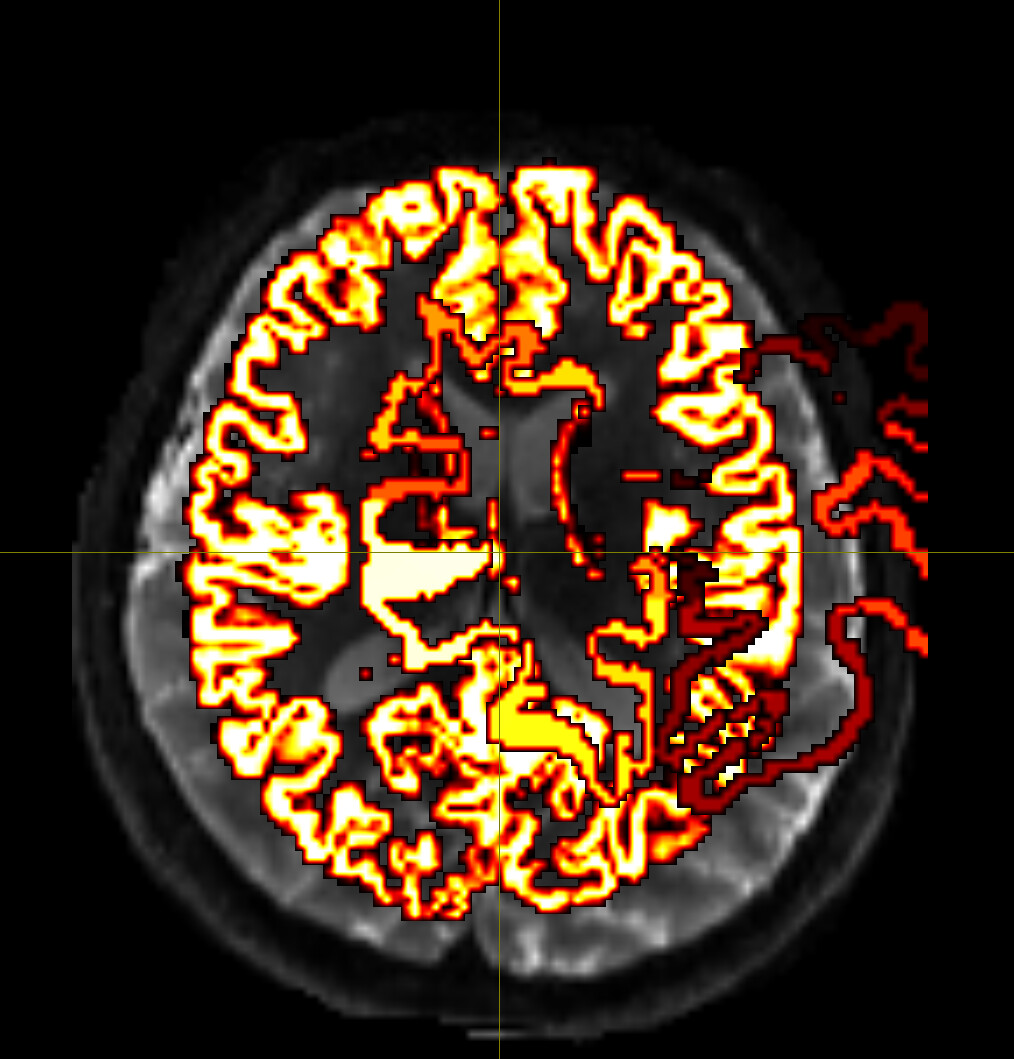

Despite extensive tuning, the final transformed atlas (DKT308_parc.mif) consistently exhibits significant bleeding (invasion) into the white matter (WM) in high-curvature sulcal regions.

I diagnosed this as over-regularization in the FNIRT process (the algorithm prioritizes smoothness over anatomical accuracy).

Visual Evidence

(Please insert the image showing the atlas bleeding into the white matter here)